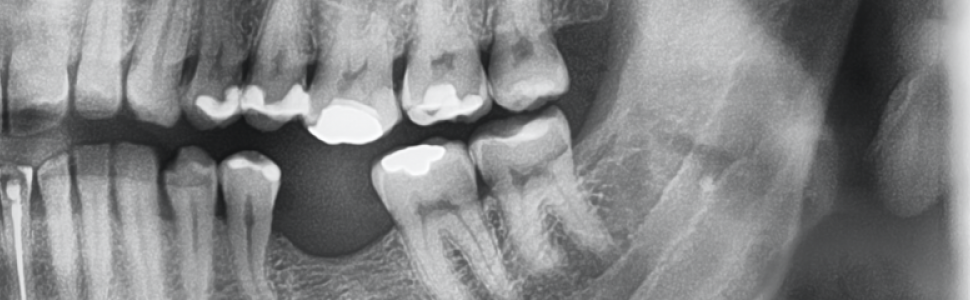

Narząd żucia jest złożoną i wyspecjalizowaną jednostką. Składa się przede wszystkim z kości, mięśni, więzadeł i zębów. Brak chociażby jednego zęba może negatywnie wpływać na cały układ stomatognatyczny, niezależnie od tego, czy dotyczy to braku zębów siecznych, kłów, zębów przedtrzonowych czy trzonowych. Dla stomatologów najważniejsze jest zachowanie zdrowej, żywej miazgi, natomiast często przywrócenie prawidłowej okluzji wymaga od nas leczenia kanałowego mimo braku patologicznych sygnałów ze strony miazgi. Celem niniejszej publikacji jest przestawienie jak ważnym etapem jest leczenie kanałowe u pacjentów z zaburzeniami okluzji. Obecność sześciu kanałów w pierwszych górnych zębach trzonowych jest niezwykle rzadkie.

The chewing organ is a complex and specialized unit. It mainly consists of bones, muscles, ligaments and teeth. The absence of even one tooth can negatively affect the entire stomatognathic system, regardless of whether it concerns the absence of incisors, canines, premolars or molars. For dentists, the most important thing is to maintain a healthy, living pulp, while restoring the correct occlusion often requires us to perform root canal treatment despite the lack of pathological signals from the pulp.The aim of this publication is to present the importance of root canal treatment in patients with occlusion disorders. The presence of six canals in the first upper molars is extremely rare.